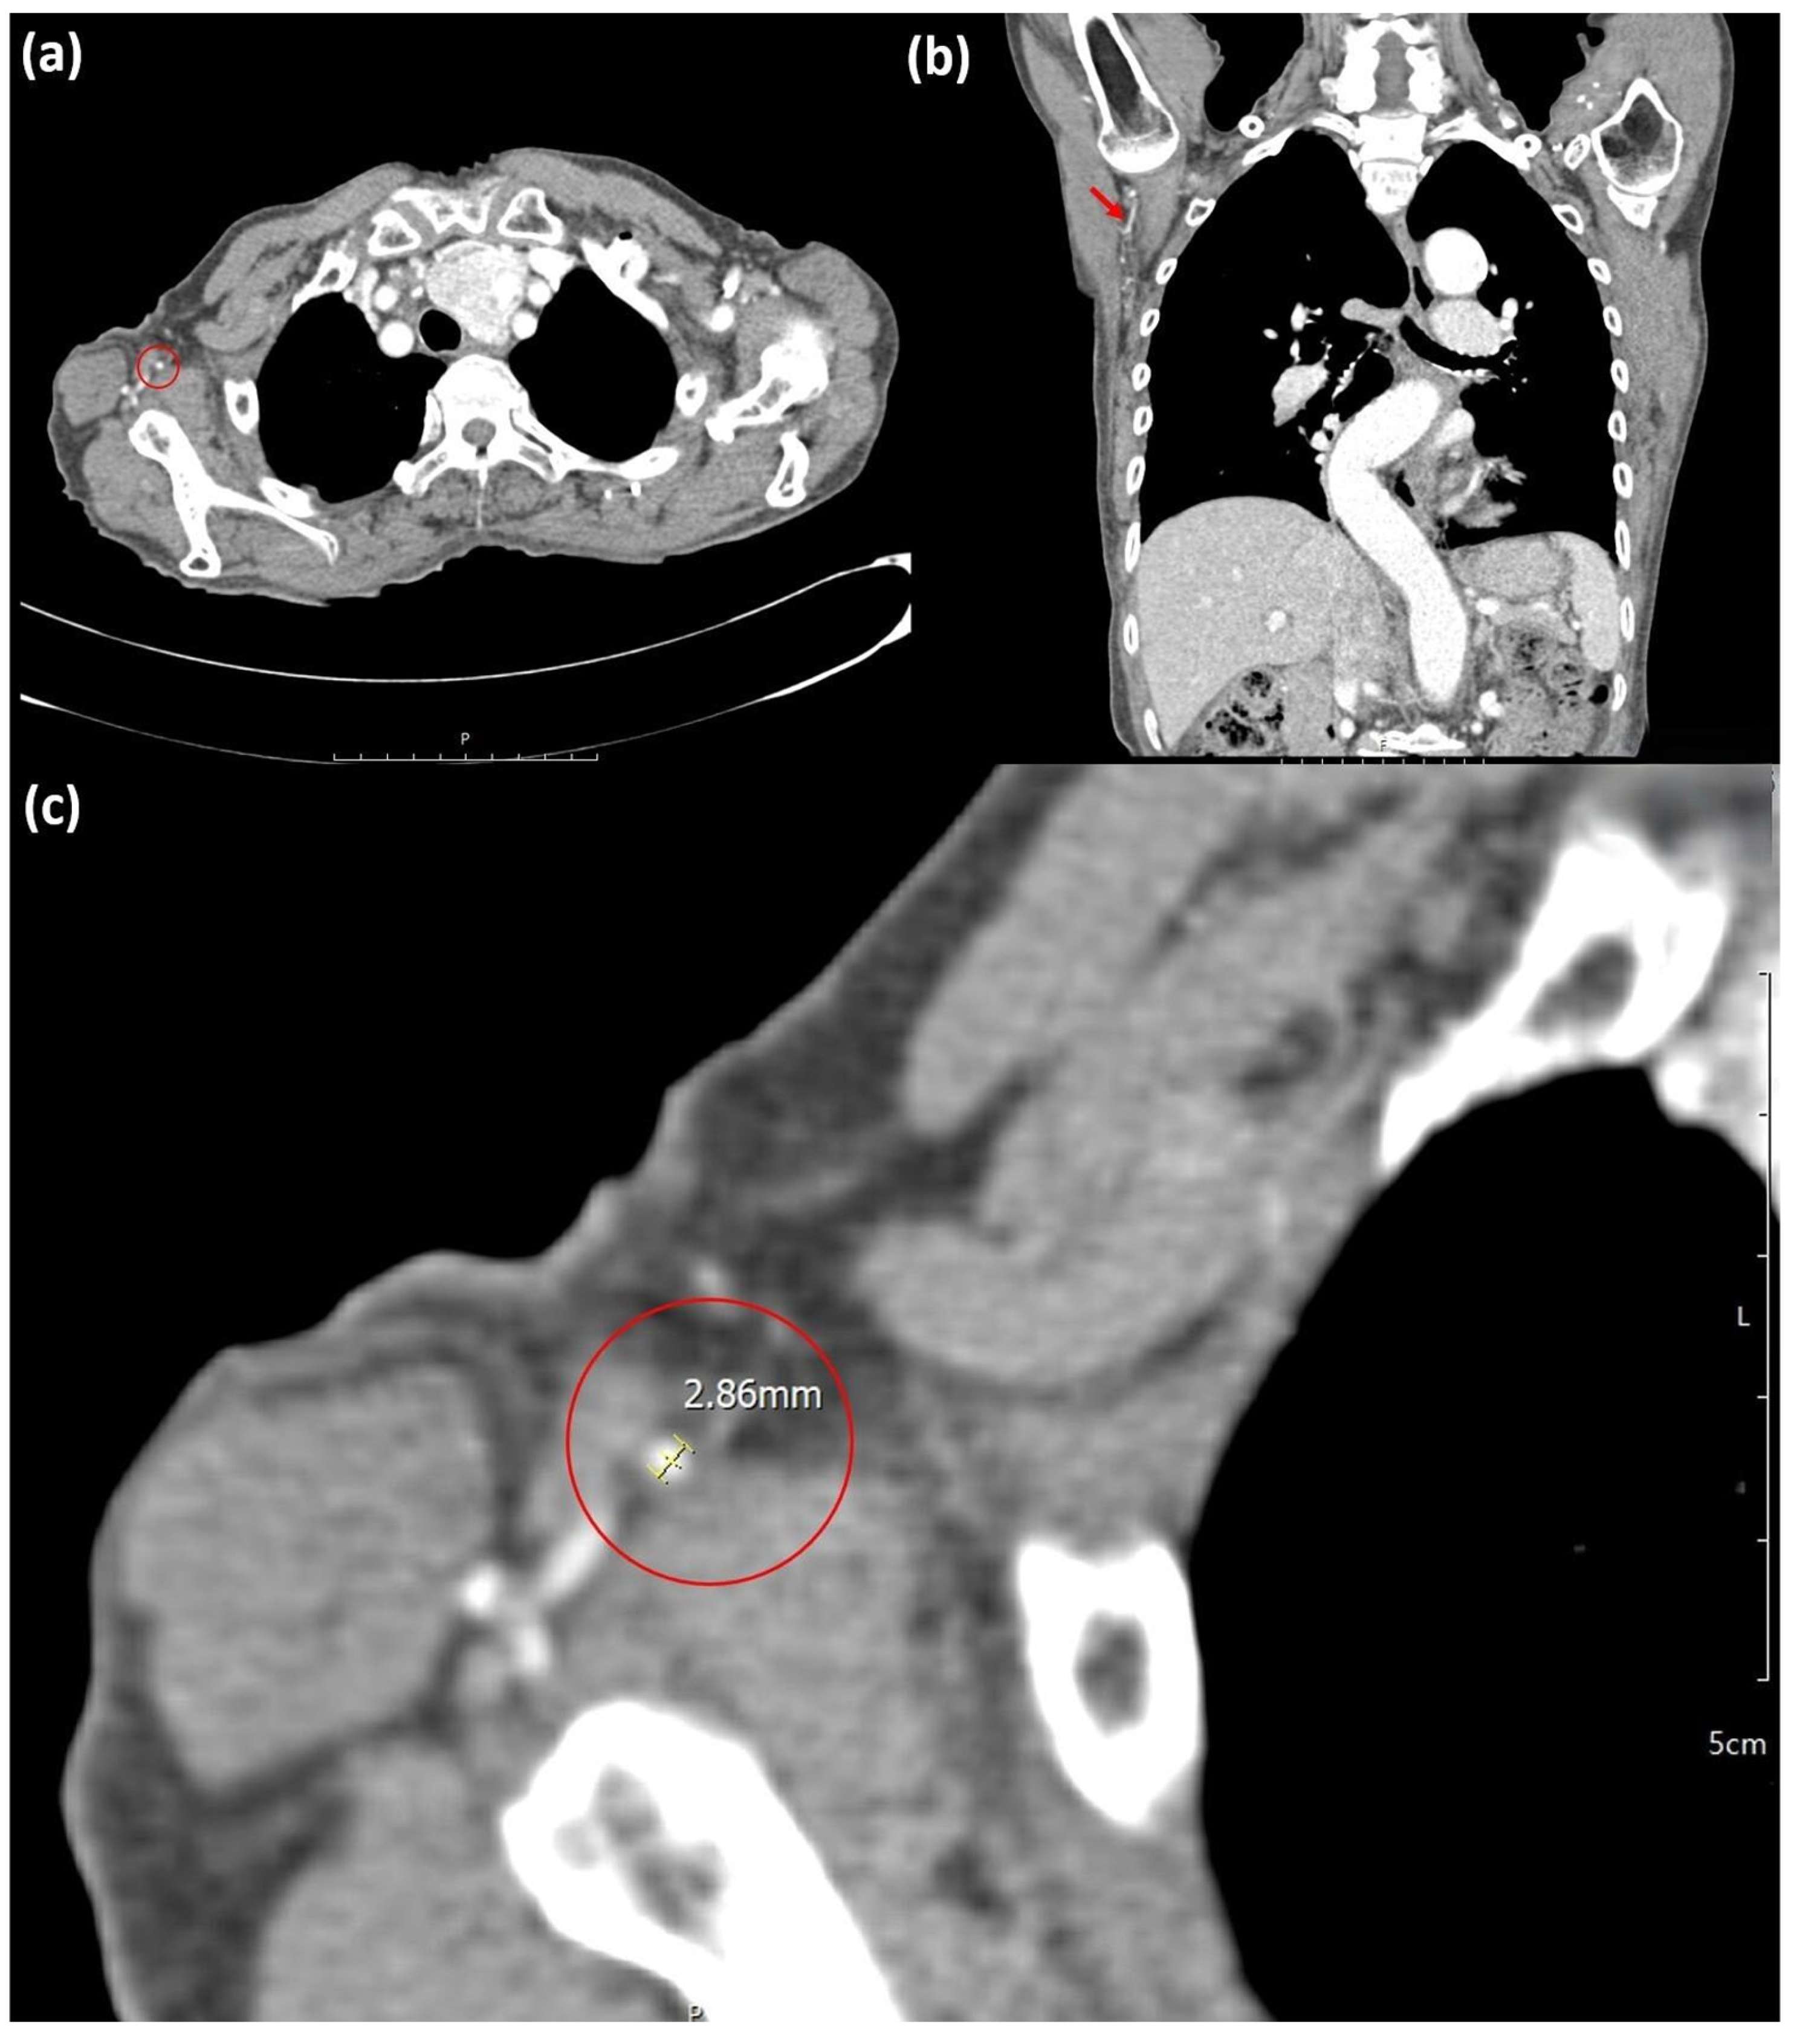

| TDA | Thoracodorsal artery |

| IMA | Internal mammary artery |